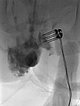

After confirmation of the diagnosis, bleomycin electrosclerotherapy was performed. For this purpose, the venous malformation was first punctured on both sides with a needle under ultrasound guidance and injected with contrast medium. Good needle placement, no major drainage veins were found.